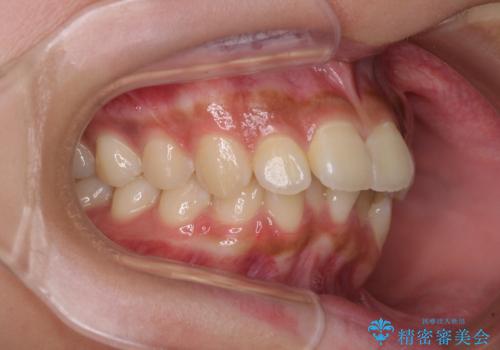

- 下唇に上顎前歯の跡がつくくらいに突出した前歯とデコボコを気にして来院された患者様です。

口元の突出感改善のため、上下左右の第一小臼歯4本を抜歯し、ワイヤー装置にて矯正治療を行うこととしました。

それほど口元の突出感が強いわけではありませんでしたが、下唇に前歯引っかかる感触が気になっていたため、抜歯矯正を行うこととしました。

上下前歯の被蓋が理想通りに改善され、患者様には大変満足していただけました。